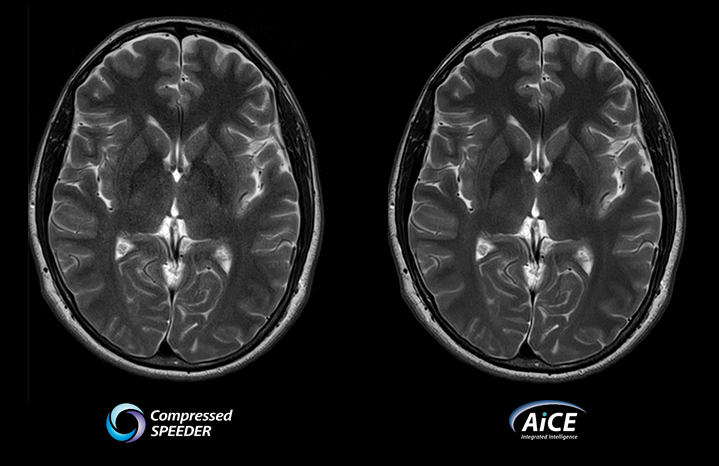

Совместите Compressed SPEEDER с AiCE DLR

- Увеличивайте разрешение за разумное время сканирования

- Улучшено качество изображения

- Повышенная клиническая уверенность

- Гибкость адаптации приобретения к текущей клинической задаче

- Увеличьте скорость или увеличьте отношение сигнал-шум и увеличьте разрешение

Время сканирования 2:00

из Vantage Galan 3T